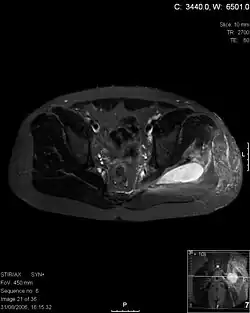

| Transverse T2 magnetic resonance imaging section through the hip region showing abscess collection in a patient with pyomyositis. | |

Axial T1 weighted fat suppressed post IV gadolinium contrast enhanced MRI image showing a mutliloculated bacterial abscess in the left gluteal muscle which grew Staphylococcus aureus (methicillin sensitive) thought to be due to tropical pyomyositis.

Coronal fat suppressed post contrast image showing a multiloculated bacterial abscess in the left gluteus minimus muscle due to tropical pyomyositis.

Coronal T2 weighted fat suppressed image showing a multiloculated fluid collection in the left gluteal musculature due to tropical pyomositis in a 12-year-old boy.